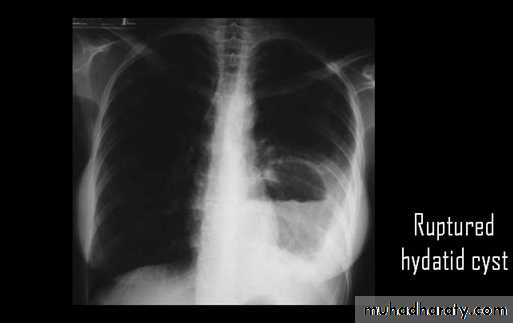

Ruptured hydatid cyst (water lily sign)

Ruptured H.C. With water lily sign .

chest practice

Un complicated Hydatid cyst of th lung , cuased by echenococus granulosis seen as well defined nodule or mass lesion .

Early rupture is sen as a cresnt air sign .ddx aspergillus ball